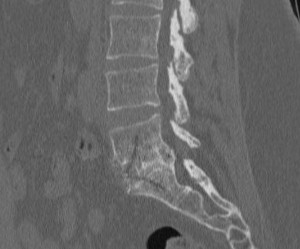

Pincement discal

Discopathie dégénérative

Notez la perte de hauteur discale

ou "pincement discal"

Les discopathies ne guérissent pas car le disque ne peut plus retrouver son aspect originel, mais si l’évolution est lente et stable progressivement (en quelques années), les douleurs aigües s’atténuent ainsi que les douleurs chroniques lombaires, le disque se tasse fortement, il peut apparaître à plus long terme des phénomènes arthrosiques.